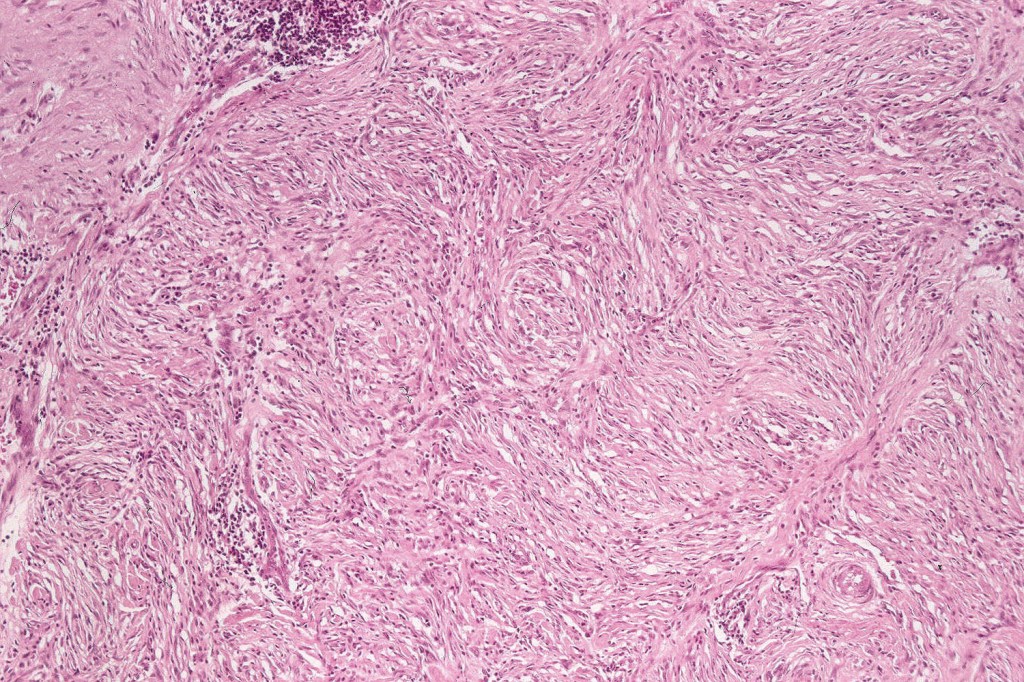

Common blue nevus

Common blue nevus shows a predilection for the backs of the hands & feet, buttocks, face & scalp althought any site can be affected. It presents as a sharply delineated approximately 1.0 cm diameter slate blue or blue/black papulo/nodule. Congenital, eruptive, targetoid, plaque & desmoplatic/hypopigmented variants are recognised. Common blue nevi have also been described in the cervix, oral mucosa, conjunctiva & sclera, breast etc.

Exceptionally, melanoma is a complication

Histologically, it is characterized by a dense population of spindled, dendritic melnanocytes & melanophages with variable fibrosis. It may sometimes represent a component of a combined nevus. Mitotic activity is not usually present and pleomorphism is absent (see atypical blue nevus below). Involvement of the arrector pili muscle is not uncommon.

Very exceptionally, blue nevus also involves the epidermis (compound blue nevus).